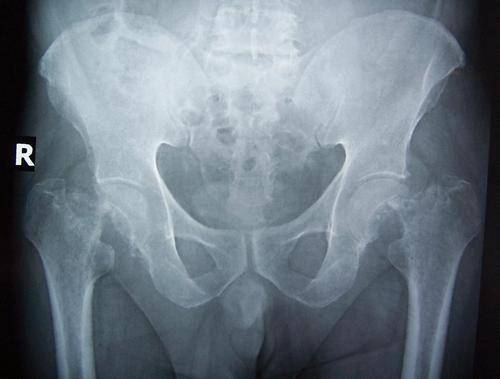

Закрытое вправление вывиха бедра относится к неотложным мероприятиям. Вывих должен быть устранен максимально быстро. Перед вправлением необходимо выполнить рентгенограмму таза в переднезадней проекции.

- Рентген. Осуществляется обязательно для всех потерпевших. Рентгенограмма делается в 2 проекциях. Подобное помогает лучше выявить расположение суставной головки бедра, выявить поражение в смежных тканях.

Какие инструментальные методы исследования привлекаются в диагностике подвывиха тазобедренного сустава? Прикладной является рентгенография сустава в двух проекциях. На рентгенологических снимках выявляют смещение головки плечевой кости из вертлужной впадины. Этого метода достаточно, чтобы выявить нарушение и определиться с нюансами врачебной тактики.